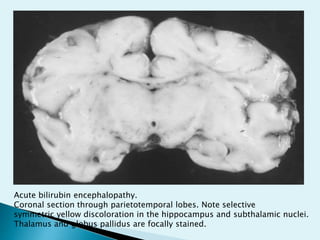

Acute bilirubin encephalopathy.

Coronal section through parietotemporal lobes. Note selective

symmetric yellow discoloration in the hippocampus and subthalamic nuclei.

Thalamus and globus pallidus are focally stained.

Acute bilirubin encephalopathy. Coronalsection through parietotemporal lobes. Note selective symmetric yellow discoloration in the hippocampus and subthalamic nuclei. Thalamus and globus pallidus are focally stained.